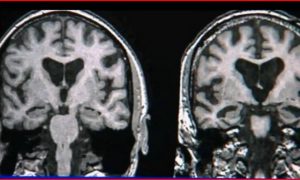

New research not only helps to explain why age is such a large risk factor for Alzheimer’s, but why higher brain circuits regulating cognition are so vulnerable to degeneration while the sensory cortex remains unaffected.

As we age, highly evolved brain circuits become susceptible to molecular changes that can lead to neurofibrillary tangles—a hallmark of Alzheimer’s disease.

Neurofibrillary tangles are made from a protein called tau, which becomes sticky and clumps together when modified in a process called phosphorylation. The new study shows that phosphorylated tau collects in neurons in higher brain circuits of the aging primate brain, but does not accumulate in neurons of the sensory cortex.